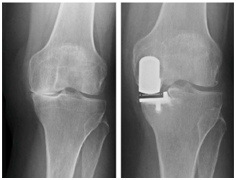

| Gambar 4: Perbandingan kondisi kerusakan sendi pada osteoarthritis (pengapuran) pada lutut. Pada pengapuran sendi yang berat dilakukan penggantian sendi untuk mengurangi nyeri dan koreksi deformitas. |

| Gambar 5: Pada pengapuran sendi pada satu sisi dapat dilakukan penggantian sendi partial (UKA). |